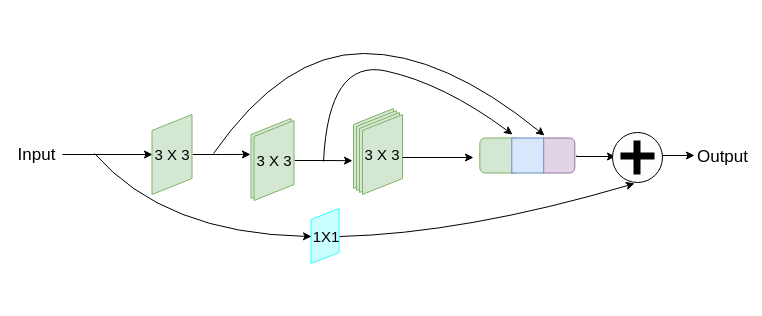

MultiResUNet

The generic design of this network is quite similar to that of U-Net, except for slight differences in the nature of convolutions in each layer and the residual path from the encoders to the decoders (Figure 2). Each layer of U-Net is replaced by a MultiRes block that contains 4 convolutions (Figure 2(b)). The skip connections of U-Net are replaced by Res Paths (Figure 2(c)) as described in [25]. The motivation of adopting this network comes from the idea that an ideal architecture should be able to assess images having diversified scales in medical image segmentation procedures. For further details readers are referred to [25].

(b) MultiRes block